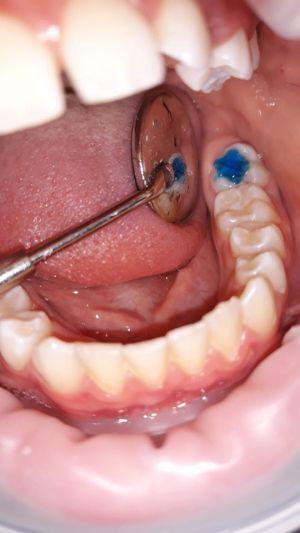

- 2. si applica sul dente un gel mordenzante a base di acido ortofosforico al 37% che ne aumenta la ruvidità superficiale per garantire una maggior adesione del prodotto sigillante;

- 3. la sigillatura si effettua utilizzando una resina composita fluida che viene applicata nei solchi dei denti per mezzo di un dispenser oppure di un apposito pennellino. La resina è di colore bianco o trasparente e da fluida viene trasformata in solida grazie all'utilizzo di una lampada definita fotopolimerizzante.